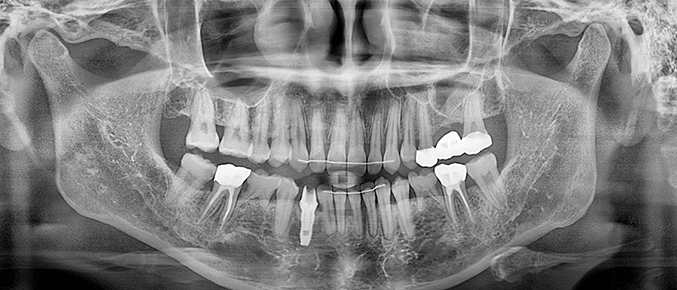

임플란트 식립이 불가능한 경우

치아를 상실한 뒤, 오랜 시간이 지나면 주위치아들이 쓰러져 임플란트를 하기 힘든 상황이 되며 쓰러진 치아는 수명이 짧아집니다.

이 경우, ‘보철전교정’을 통해 쓰러진 치아를 바로세워주고 적절한 임플란트 치료가 가능해집니다.